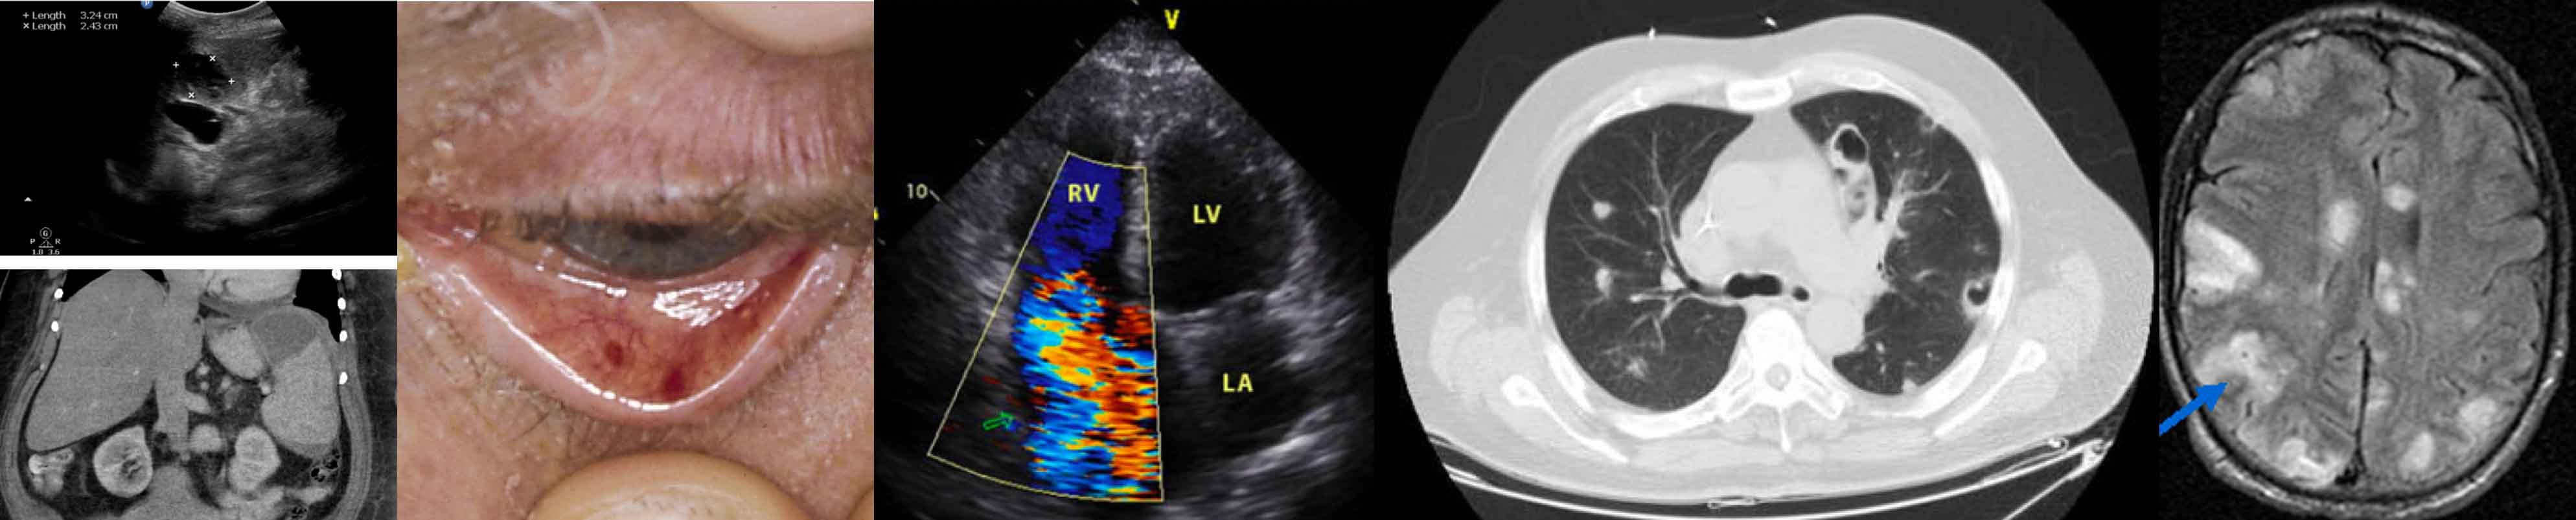

Пятна Рота Фото

Пятна Рота Фото 29 фотографий